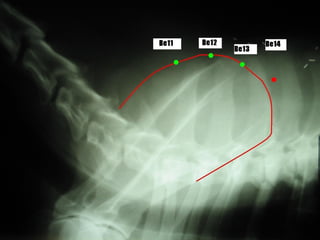

P B13 Per B14

C B15 F B18

VB B19 BP B20

E B21 TA B22

R B23 IG B25

ID B27 B B28

Pontos de assentimentoPontos de assentimento::

B 13 T3 – T4

1.5 tsun lateral à borda caudal do processo

espinhoso da 3ª vértebra torácica

Assentimento do P

Lung Shu Point

B 14 T4 – T5

espinhoso da 4ª vértebra torácica

Assentimento do Per

Pericardium Shu Point

B 15 T5 – T6

espinhoso da 5ª vértebra torácica

Assentimento do C

Heart Shu Point

PULA UMA VÉRTEBRA!